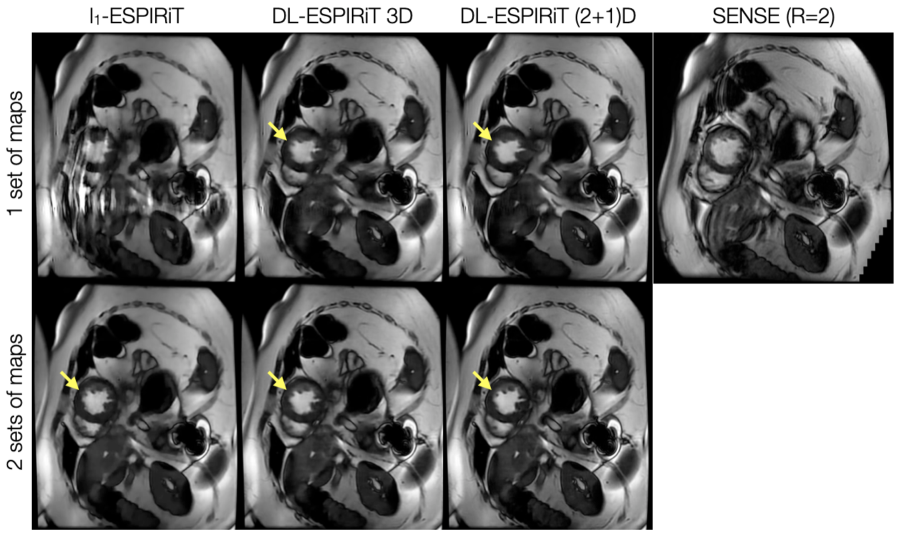

As shown by Fig. 3, DL-ESPIRiT reconstructions with one set of ESPIRiT maps show residual ghosting artifacts originating from sensitivity map errors in areas with anatomy overlap. By augmenting the signal model with two sets of ESPIRiT maps, the DL-ESPIRiT reconstruction is able to reconstruct overlapped components separately without ghosting artifacts. A corresponding video is shown in Supporting Information Video S1. An additional video of a 2-chamber view with anatomy overlap is shown in Supporting Information Video S2. This result is further demonstrated in a prospectively undersampled dataset shown in Figure 4 with a corresponding video shown in Supporting Information Video S3.

Figure 3: A fully-sampled 2D cardiac cine acquisition in the standard 4-chamber view is retrospectively undersampled to simulate 10X acceleration, and then reconstructed using l1subscript𝑙1l_{1}-ESPIRiT and (2+1)D DL-ESPIRiT with one and two sets of ESPIRiT maps. Anatomy overlap is present along the chest wall (blue arrow), which causes significant ghosting along the phase encoding direction of the single-set l1subscript𝑙1l_{1}-ESPIRiT reconstruction (red arrows). Some ghosts are present in the single-set (2+1)D DL-ESPIRiT reconsruction (yellow arrows), but they are largely reduced compared to the single-set l1subscript𝑙1l_{1}-ESPIRiT reconstruction. Both double-set reconstructions are able to capture overlapping anatomies, separate them into two complex-valued channels (one for each set of maps), and completely eliminate ghosting artifacts. A corresponding video of these images is shown in Supporting Information Video S1.

Figure 4: With IRB approval, a prospectively undersampled (R=12) dataset is acquired from a pediatric patient within a single breath-hold on a 1.5T scanner. The images shown are reconstructed using l1subscript𝑙1l_{1}-ESPIRiT, 3D DL-ESPIRiT, and (2+1)D DL-ESPIRiT algorithms with one and two sets of ESPIRiT maps. For reference, a standard cardiac cine image acquired with 2-fold uniform undersampling (R=2) and reconstructed using SENSE is shown in the top right. Subtle motion artifacts arising from respiratory motion are shown in this image because the patient had difficulty holding their breath. Anatomy overlap is present along the chest wall, which causes severe aliasing on top of the heart as shown in the l1subscript𝑙1l_{1}-ESPIRiT reconstruction with one set of sensitivity maps. This artifact manifests as blurring in DL-ESPIRiT reconstructions with one set of ESPIRiT maps, and is most evident along left ventricle papillary muscles (yellow arrow). Both l1subscript𝑙1l_{1}-ESPIRiT and DL-ESPIRiT reconstructions resolve these artifacts when two sets of ESPIRiT maps are used. Corresponding videos for each reconstruction are shown in Supporting Information Video S3.